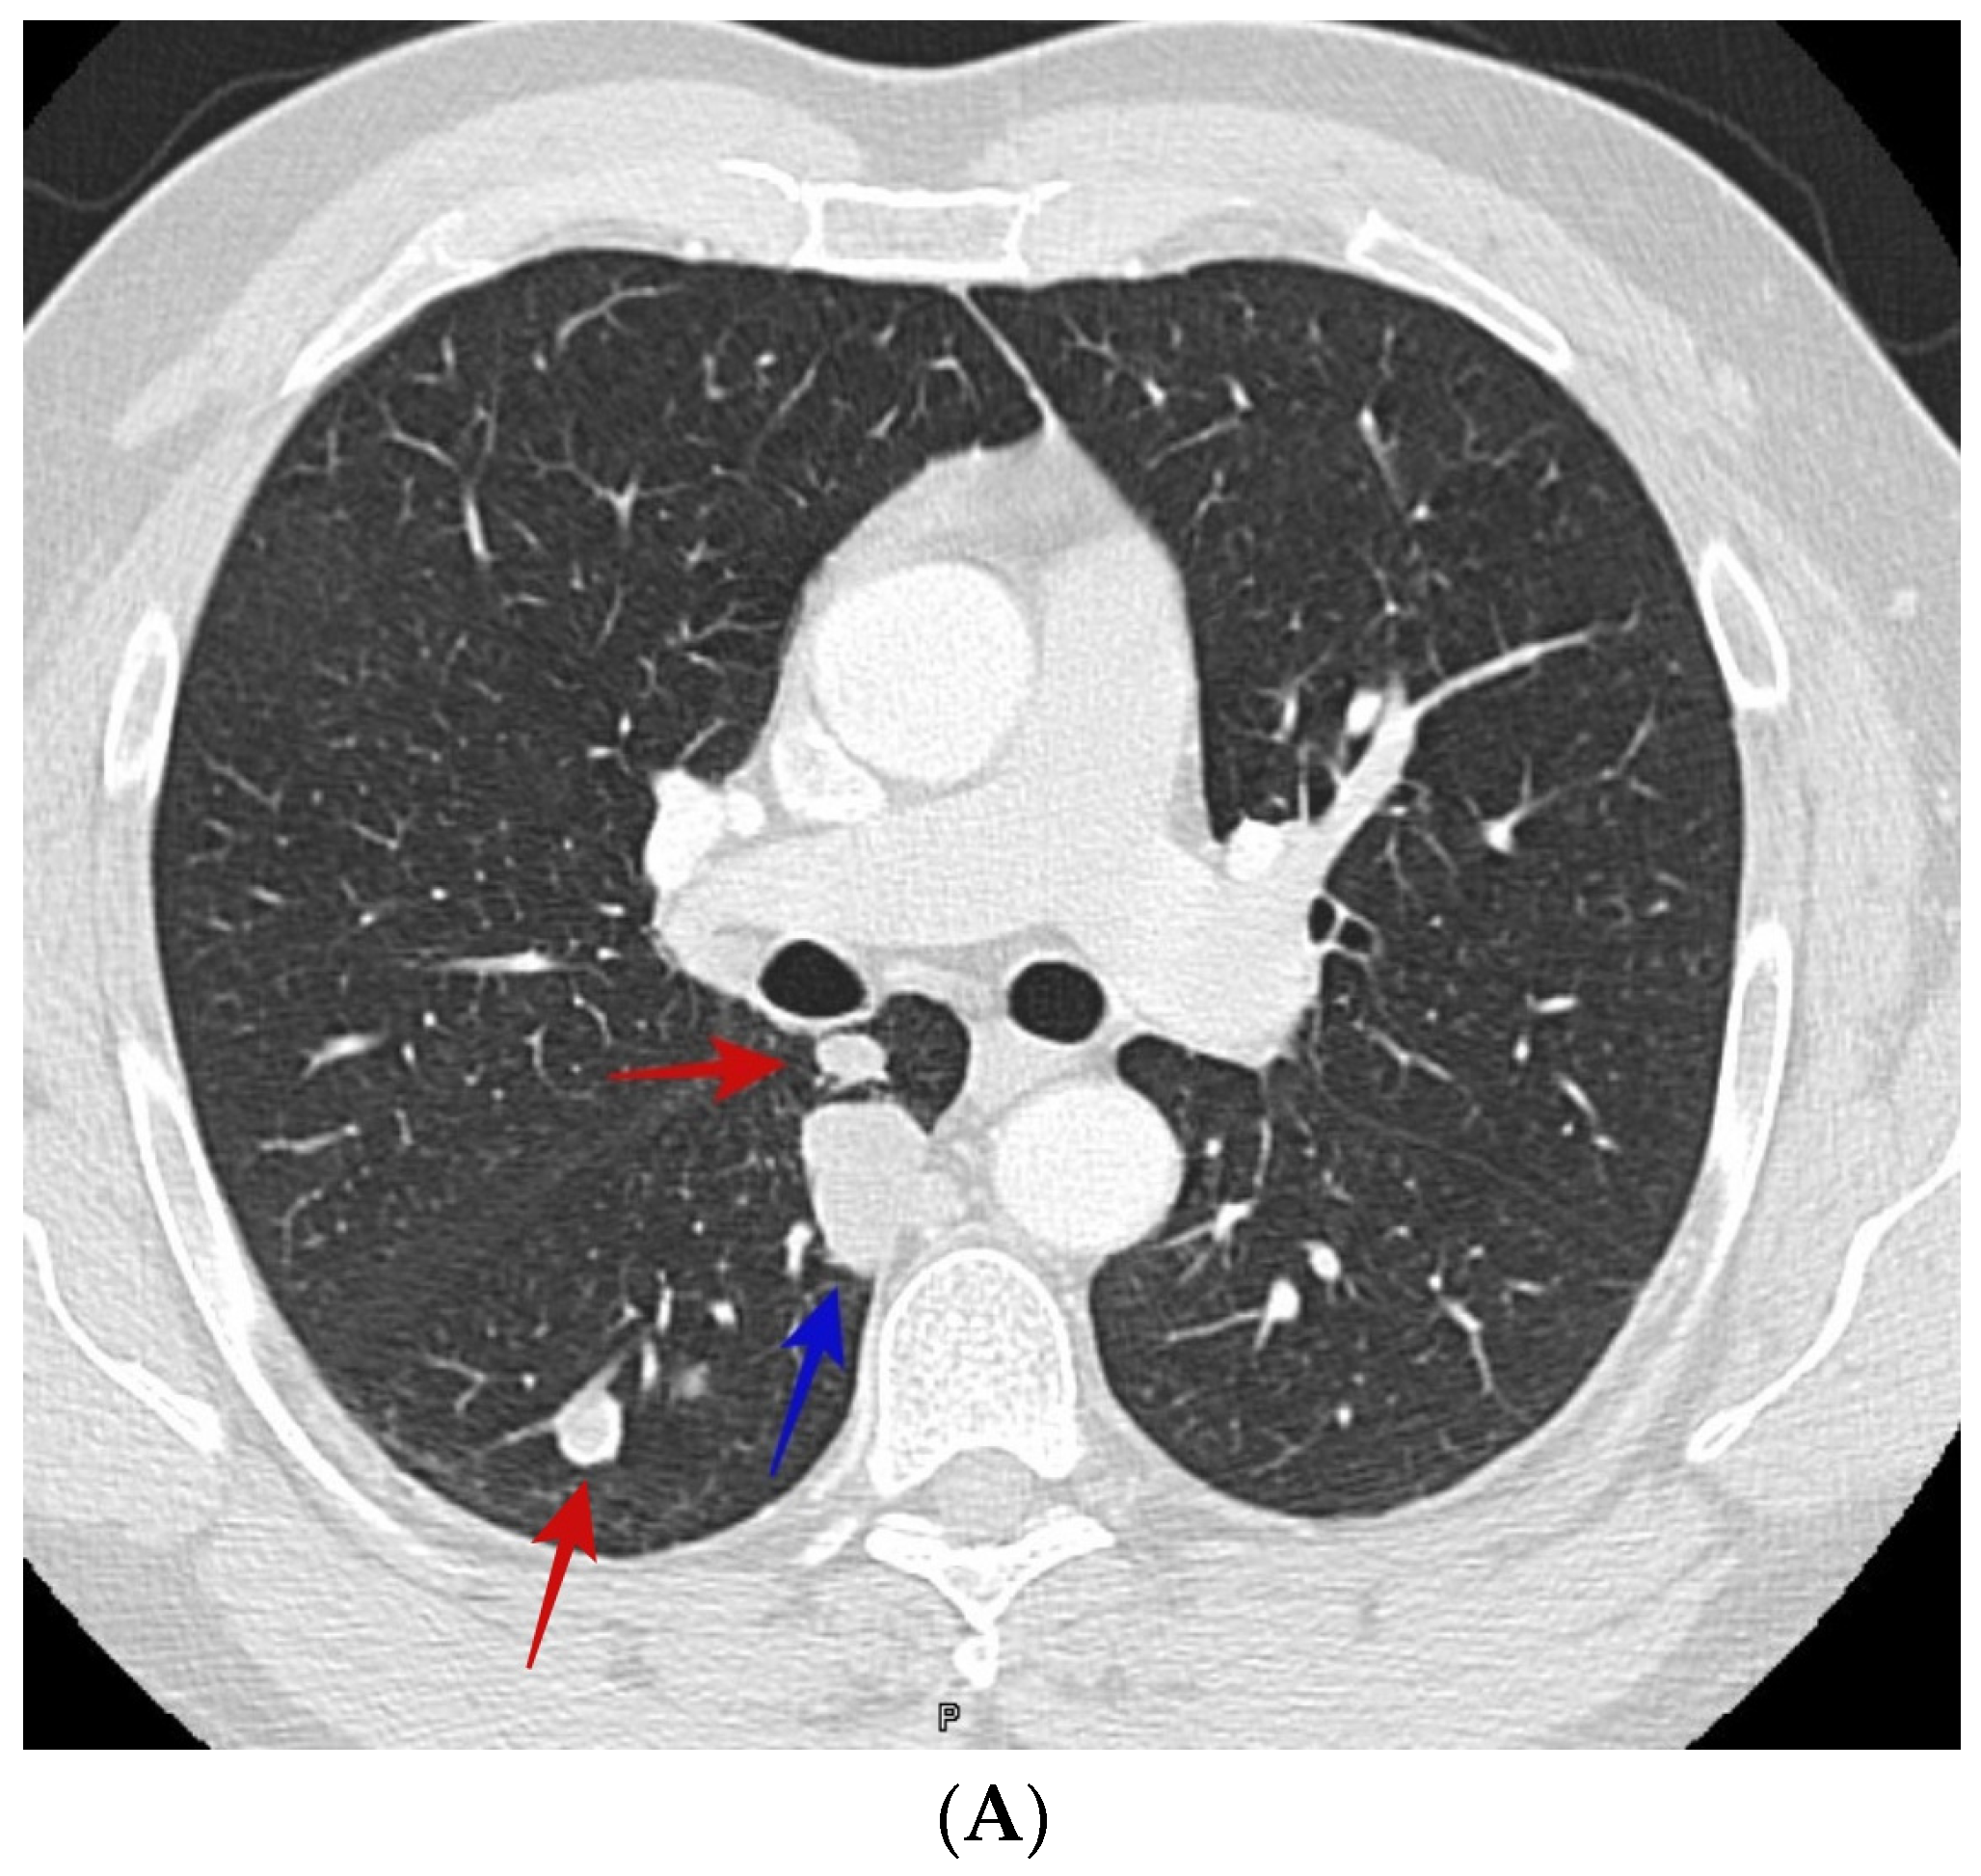

TitleIntrapulmonary Percussive Ventilation (IPV) | Clinical Evidence